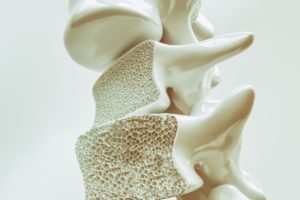

There may be a new treatment method for osteoporosis in the works. Researchers at Strathclyde University will use volunteers with paralyzed limbs to test their new treatment. Although osteoporosis can affect all people, it affects those with paralysis more so as they are unable to move.

There may be a new treatment method for osteoporosis in the works. Researchers at Strathclyde University will use volunteers with paralyzed limbs to test their new treatment. Although osteoporosis can affect all people, it affects those with paralysis more so as they are unable to move.

It is known that physical activity can help protect bones from osteoporosis. In those who cannot partake in physical activity, bones can become weaker, resulting in a higher risk of osteoporosis.